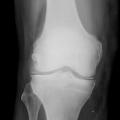

Ostéochondrose apophysaire de la rotule

FRACTURES OSSEUSES

ENFANT

EXERCICE PHYSIQUE

Image